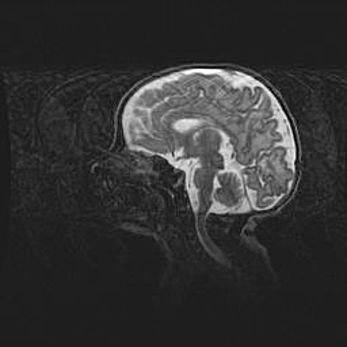

Аномалия Денди-Уокера. Признаки гипоплазии мозолистого тела.

Возраст: 5 месяцев 3 дня

Вес: 5550 г

Пол: мужской

Окружность головы: 39 см

Срок гестации: 40 недель

Аномалия Денди-Уокера – это порок развития головного мозга, для которого характерна триада симптомов: гипотрофия или аплазия червя мозжечка и/или полушарий мозжечка, расширение четвёртого желудочка с формированием ликворной кисты задней черепной ямки, гипертензионная гидроцефалия различной степени.

Гипоплазия мозолистого тела относится к дефектам внутриутробного этапа развития мозговой ткани, возникающим в процессе закладки структур головного мозга, что происходит на начальных этапах развития эмбриона.